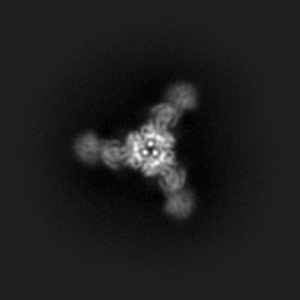

HMPV F v3-B in complex with MPE33 Fab

Single-particle4.79 Å

Sample: HMPV F v3-B in complex with MPE33